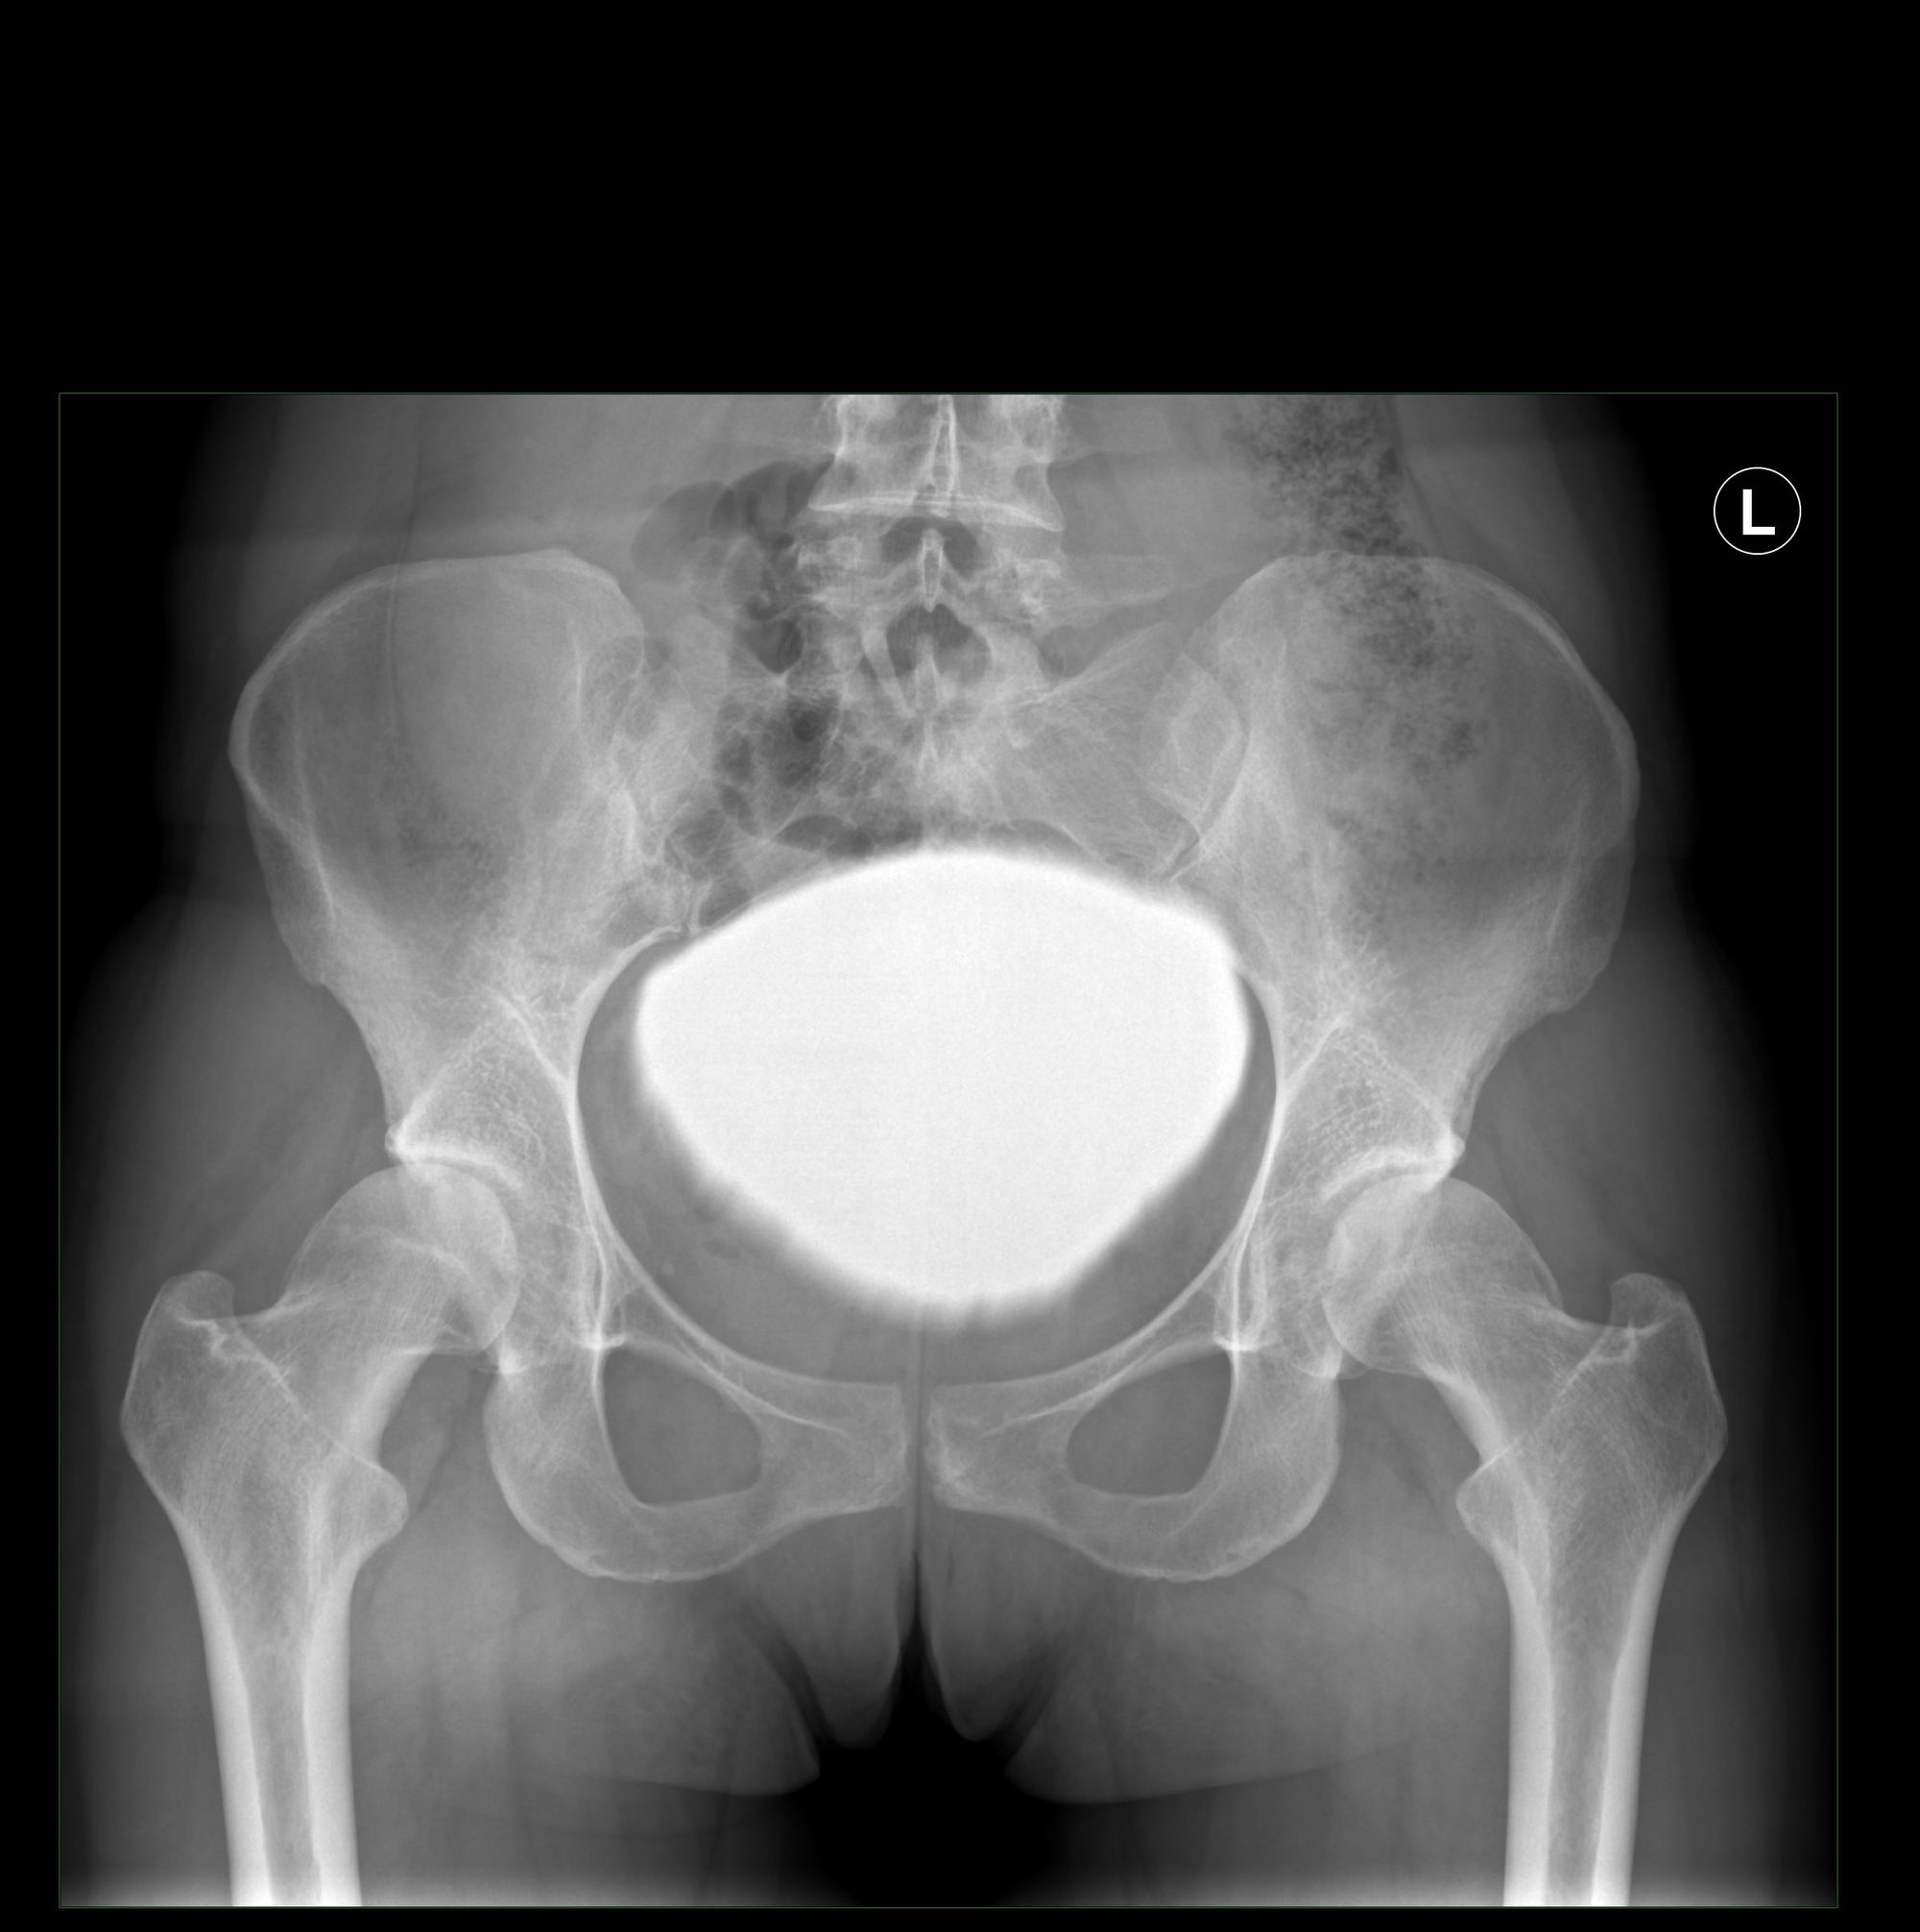

Acetabular dysplasia (AD) as well as femoroacetabular impingement (FAI) are frequent disorders and play an important role in the development of hip osteoarthritis (OA). The two entities can occur independent from each other, but also in combination (fig. 1).

The indication for POA is radiographically confirmed acetabular dysplasia with a lateral center-edge (LCE) angle of less than 25° and hip pain for at least 6 months, which does not adequately respond to conservative therapy. The decision about additionally necessary intra-articular procedures is based on clinical and imaging findings. In order to search for potential morphologic damages resulting from asphericity of the femoral head, each patient with radiographically confirmed AD undergoes a standardized MRI investigation with radial sequences and measurement of femoral torsion. If patients show less than 10° internal rotation of the hip with or without a positive anterior impingement test, a normal femoral antetorsion and there is evidence of a cam pathology (alpha angle >50°), head-neck recontouring is performed together with the osteotomy. The choice of bump resection through arthrotomy alone or additional arthroscopically-assisted surgery is depending on the diagnosis of chondrolabral pathology on preoperative MRI investigation. If signs of chondrolabral pathology (i.e. labral tears, lesions of the chondrolabral transition zone) are present, arthroscopically assisted exposure and treatment of the lesion on a traction table is performed. In cases with abnormal acetabular version (either retroversion or elevated anteversion as diagnosed on native pelvic radiographs and confirmed by MRI), the orientation of the acetabular fragment is corrected through the osteotomy. In significantly elevated femoral anteversion (>30°) or retroversion, an additional intertrochanteric osteotomy may be considered, which can also be performed on the traction table. Contraindications for simultaneous PAO and cam-treatment are advanced radiographic OA (Kellgren-Lawrence Grade 3 and 4), incongruency of the joint space on pelvic antero-posterior radiographs or abduction view, and a patient age over 50 years.

Crutches are recommended for about 8-10 weeks. Routine thromboprophylaxis is administered for the first 6 weeks. Fig. 8 shows the treatment result of a 22 year old male with a combination of AD and cam-FAI, where head-neck osteochondroplasty and microfracturing of acetabular cartilage defects have been performed.

Fig. 8: Combined AD and cam-FAI with pre-op radiographs (8a, b), pre-op radial MRI (8c),

postoperative radiographs after PAO with cam resection and microfracturing (8d, e) and final result after 12 years (8f, g)